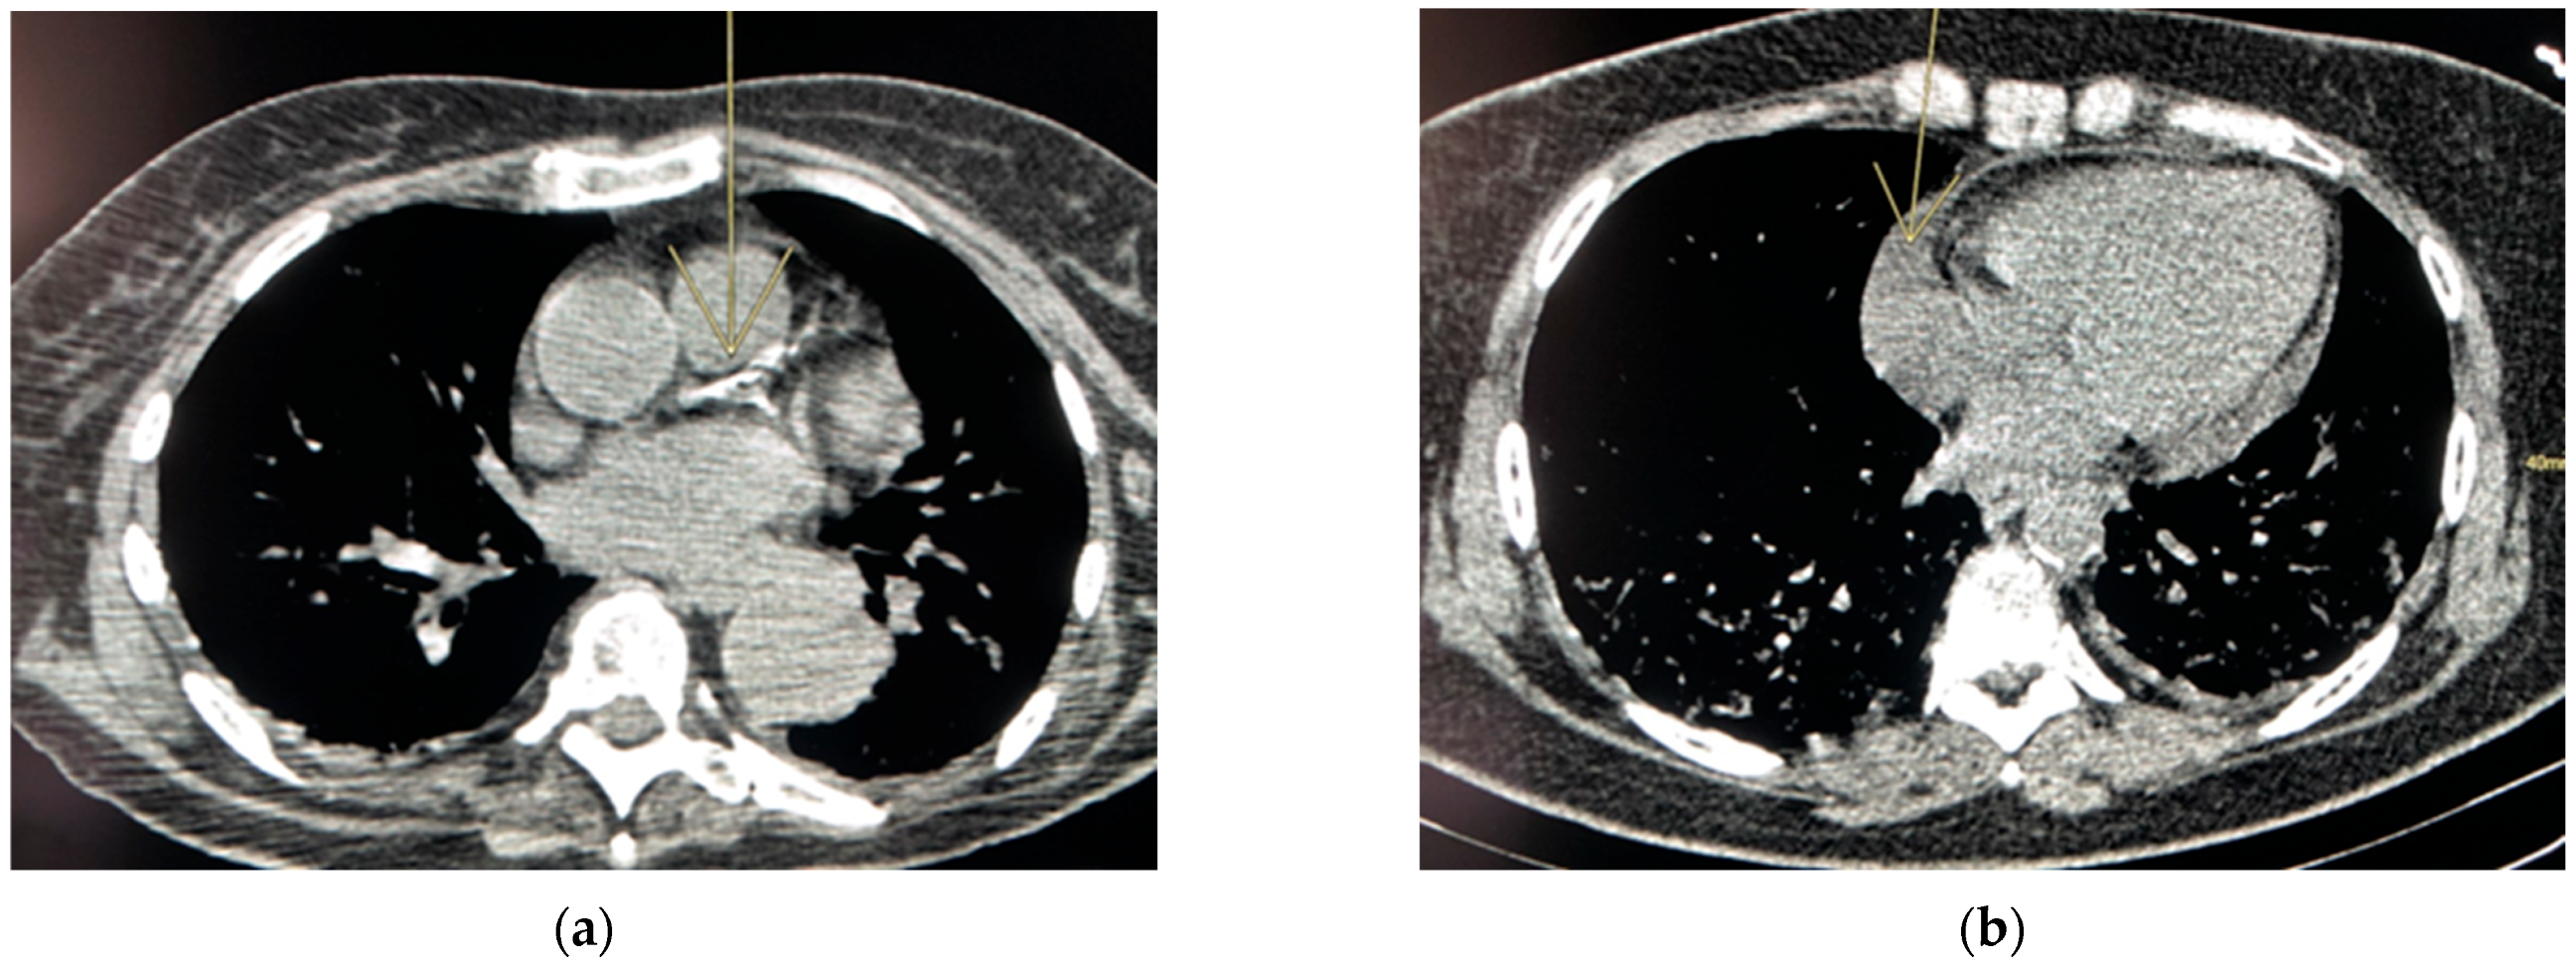

Risk Lesions